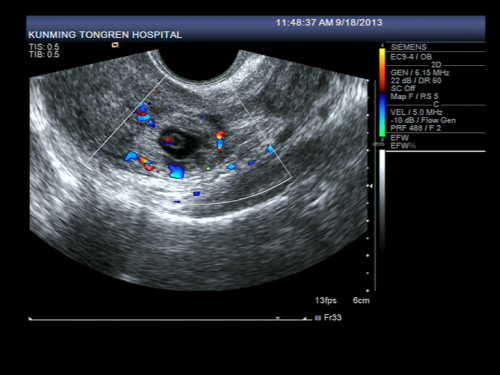

受精卵在子宫体腔以外的地方着床成为异位妊娠,习称宫外孕,是妇产科常见的急腹症,发病率约1%,是孕产妇的主要死亡原因之一。根据受精卵在子宫体外种植部位不同可分为:输卵管妊娠、卵巢妊娠、腹腔妊娠、阔韧带妊娠、宫颈妊娠,其中以输卵管妊娠最常见,占95%左右,而壶腹部妊娠占75%。一般来讲,输卵管有异常的育龄妇女如输卵管炎症、输卵管手术史、输卵管发育不良或功能异常者易导致异位妊娠,其他例如辅助生殖技术、避孕失败、子宫肌瘤或者子宫内膜异位症也容易导致疑问妊娠的发生。根据输卵管妊娠的病理特点可分为以下4型:流产型、破裂型、陈旧性、继发性,主要临床表现是停经后腹痛与阴道出血,当腹腔内出血量大或者疼痛剧烈时可出现晕厥与休克,超声检查下可观察到:宫腔内空虚,宫旁出现似孕囊样包块或者不均质包块,盆腔积液等等,再结合病史、血HCG、尿HCG结果分析,一般可诊断早期异位妊娠。